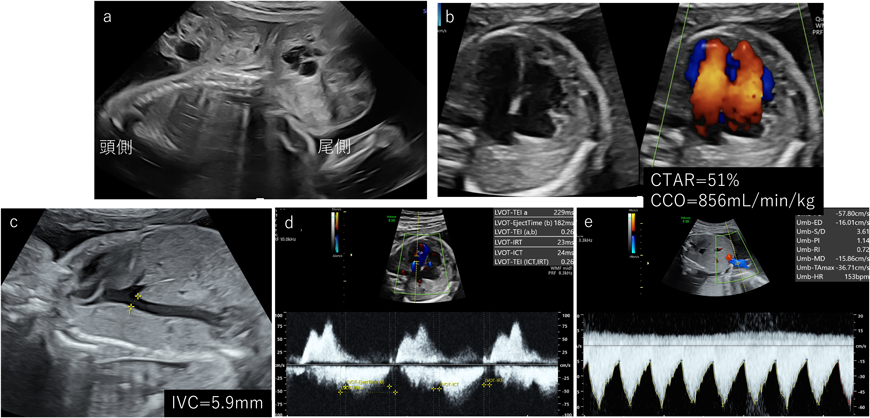

胎児の高拍出性心不全の場合,心拡大がきっかけとなって原因となる疾患が診断されることもある.胎児貧血が原因となる場合にはMCA-PSVの上昇を認める.動静脈奇形や血管腫,仙尾部奇形腫などは原因となる部位にカラードプラで豊富な血流を認める.高拍出性の場合には心不全といいながらも胎児心機能自体は保たれていることが多い.そのため代償できている間は心機能の評価項目に変化は認めない.CCOが症状の進行に鋭敏といわれていて,700–800 mL/min/kgを超えてくると胎児水腫のリスクが上昇する18).胎児の全身状態を評価する目的で静脈管のPIの上昇が参考になるという報告もある19).SCTの検討では下大静脈の増大(>6 mm)や600 mL/min/kg以上のCCOの増大が早期での心不全を検出できる可能性がある20). Fig. 6にAltman type IのSCTの症例を提示している.本症例は妊娠19週で腫瘍体積/胎児体重比が0.34(>0.12)であり,予後不良が予測されていた(Fig. 6a).妊娠25週でCTAR=51%, CCO>800 mL/min/kg, IVC=5.9 mm(Fig. 6b, c)であり,左室のMPIをはじめとした心機能や胎児の動静脈血流は保たれていた(Fig. 6d, e)が,ちょうどこの時点から皮下浮腫を認め始め,胎児水腫の傾向を呈した.

Pediatric Cardiology and Cardiac Surgery 40(2): 103-112 (2024)

Fig. 6 高拍出性心不全(仙尾部奇形腫)の一例

CCO=総心拍出量,IVC=下大静脈.CTAR, cardiothoracic area ratio